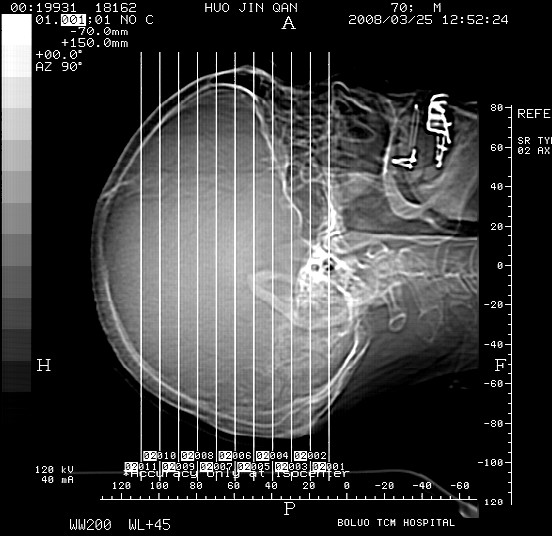

以下是引用随光逐影在2008-3-25 20:15:00的发言:[br]双侧额颞顶部亚急性(或慢性)硬膜下血肿。

以下是引用liuyue在2008-3-26 18:57:00的发言:[br]以下是引用随光逐影在2008-3-25 20:15:00的发言:[br]双侧额颞顶部亚急性(或慢性)硬膜下血肿。 [br]支持![br]可以无明显外伤病史,老年人可以在激烈摇晃或轻微头部碰创头部时,发生硬膜下出血.